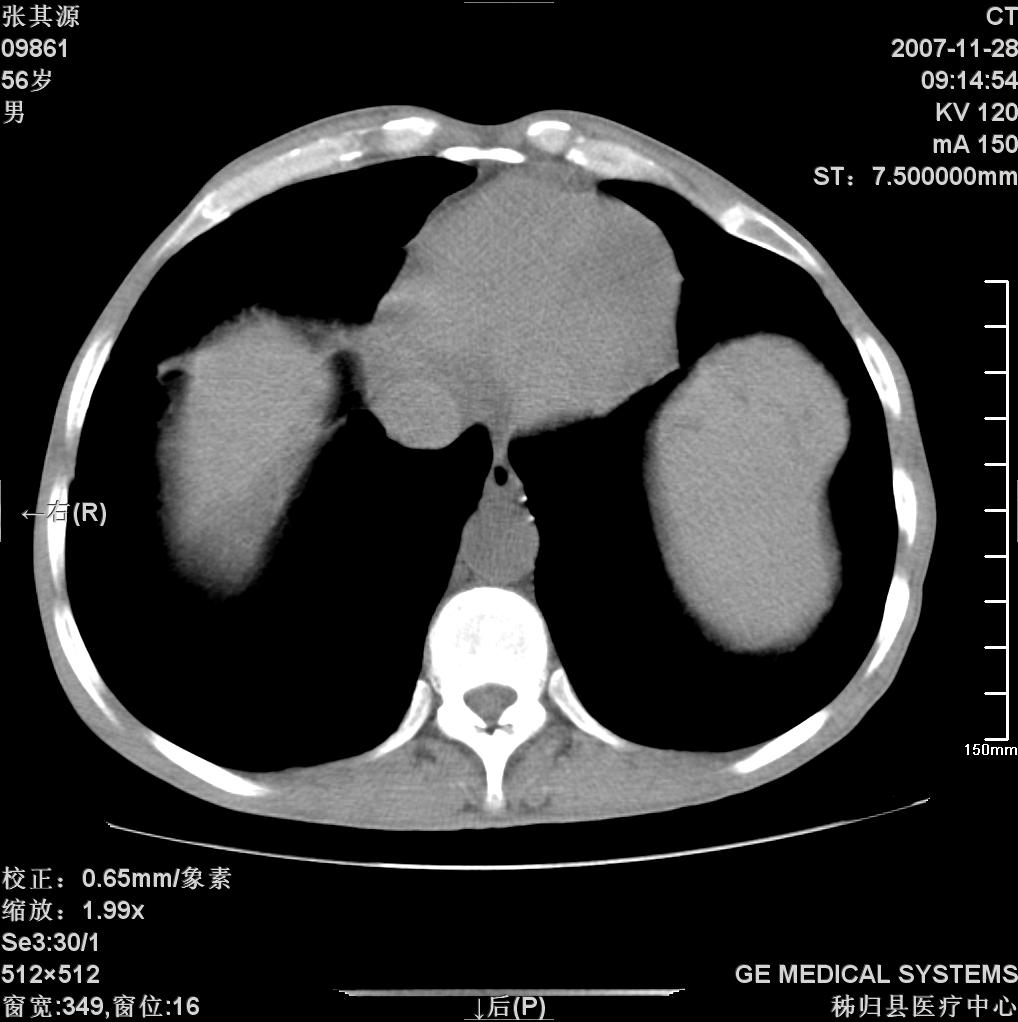

患者因阻塞性黄疸入院,发病前10天持续中等程度发烧.术前检查发现两肺弥漫性病变,请各位大虾会诊,除了考虑急性血源性肺结核外,还有其他什么疾病可能.

补充一下,该患者没有与尘肺相关职业史。请大家帮忙会诊一下,外科医生打算为其做胆总管肿瘤做手术的,现在在等我们的结果。谢谢各位了。

双肺多发粟粒样病灶,右肺胸膜下结节样病灶,气管前腔静脉后及隆突下均见肿大淋巴结,结合胆道肿瘤病史首先考虑转移。另外心影密度略低,时间格显示,是否有贫血?查明白再手术吧!